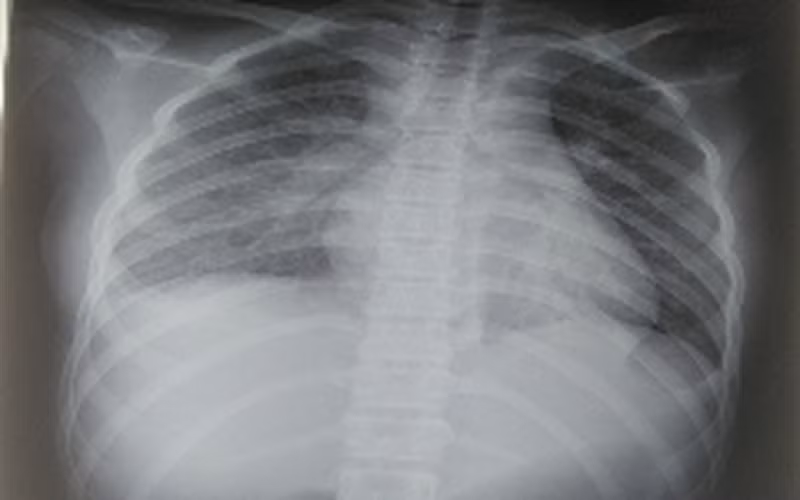

Các xét nghiệm cho thấy bệnh nhi bị tổn thương nhiều cơ quan, trong đó, phổi có tổn thương mờ dạng kẽ vùng rốn phổi 2 bên; tim có tràn dịch màng ngoài tim; các chỉ số men gan cũng tăng gấp 2 lần. Đặc biệt là các chỉ số viêm tăng rất cao.

Phim chụp tổn thương phổi của bệnh nhi. Ảnh: BV.